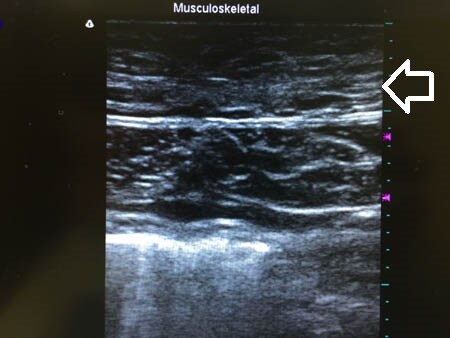

3Dタッチビュー(=超音波)で

皮下脂肪層の変化を見てみましょう。

上の画像の部分をつまんでみましょう。